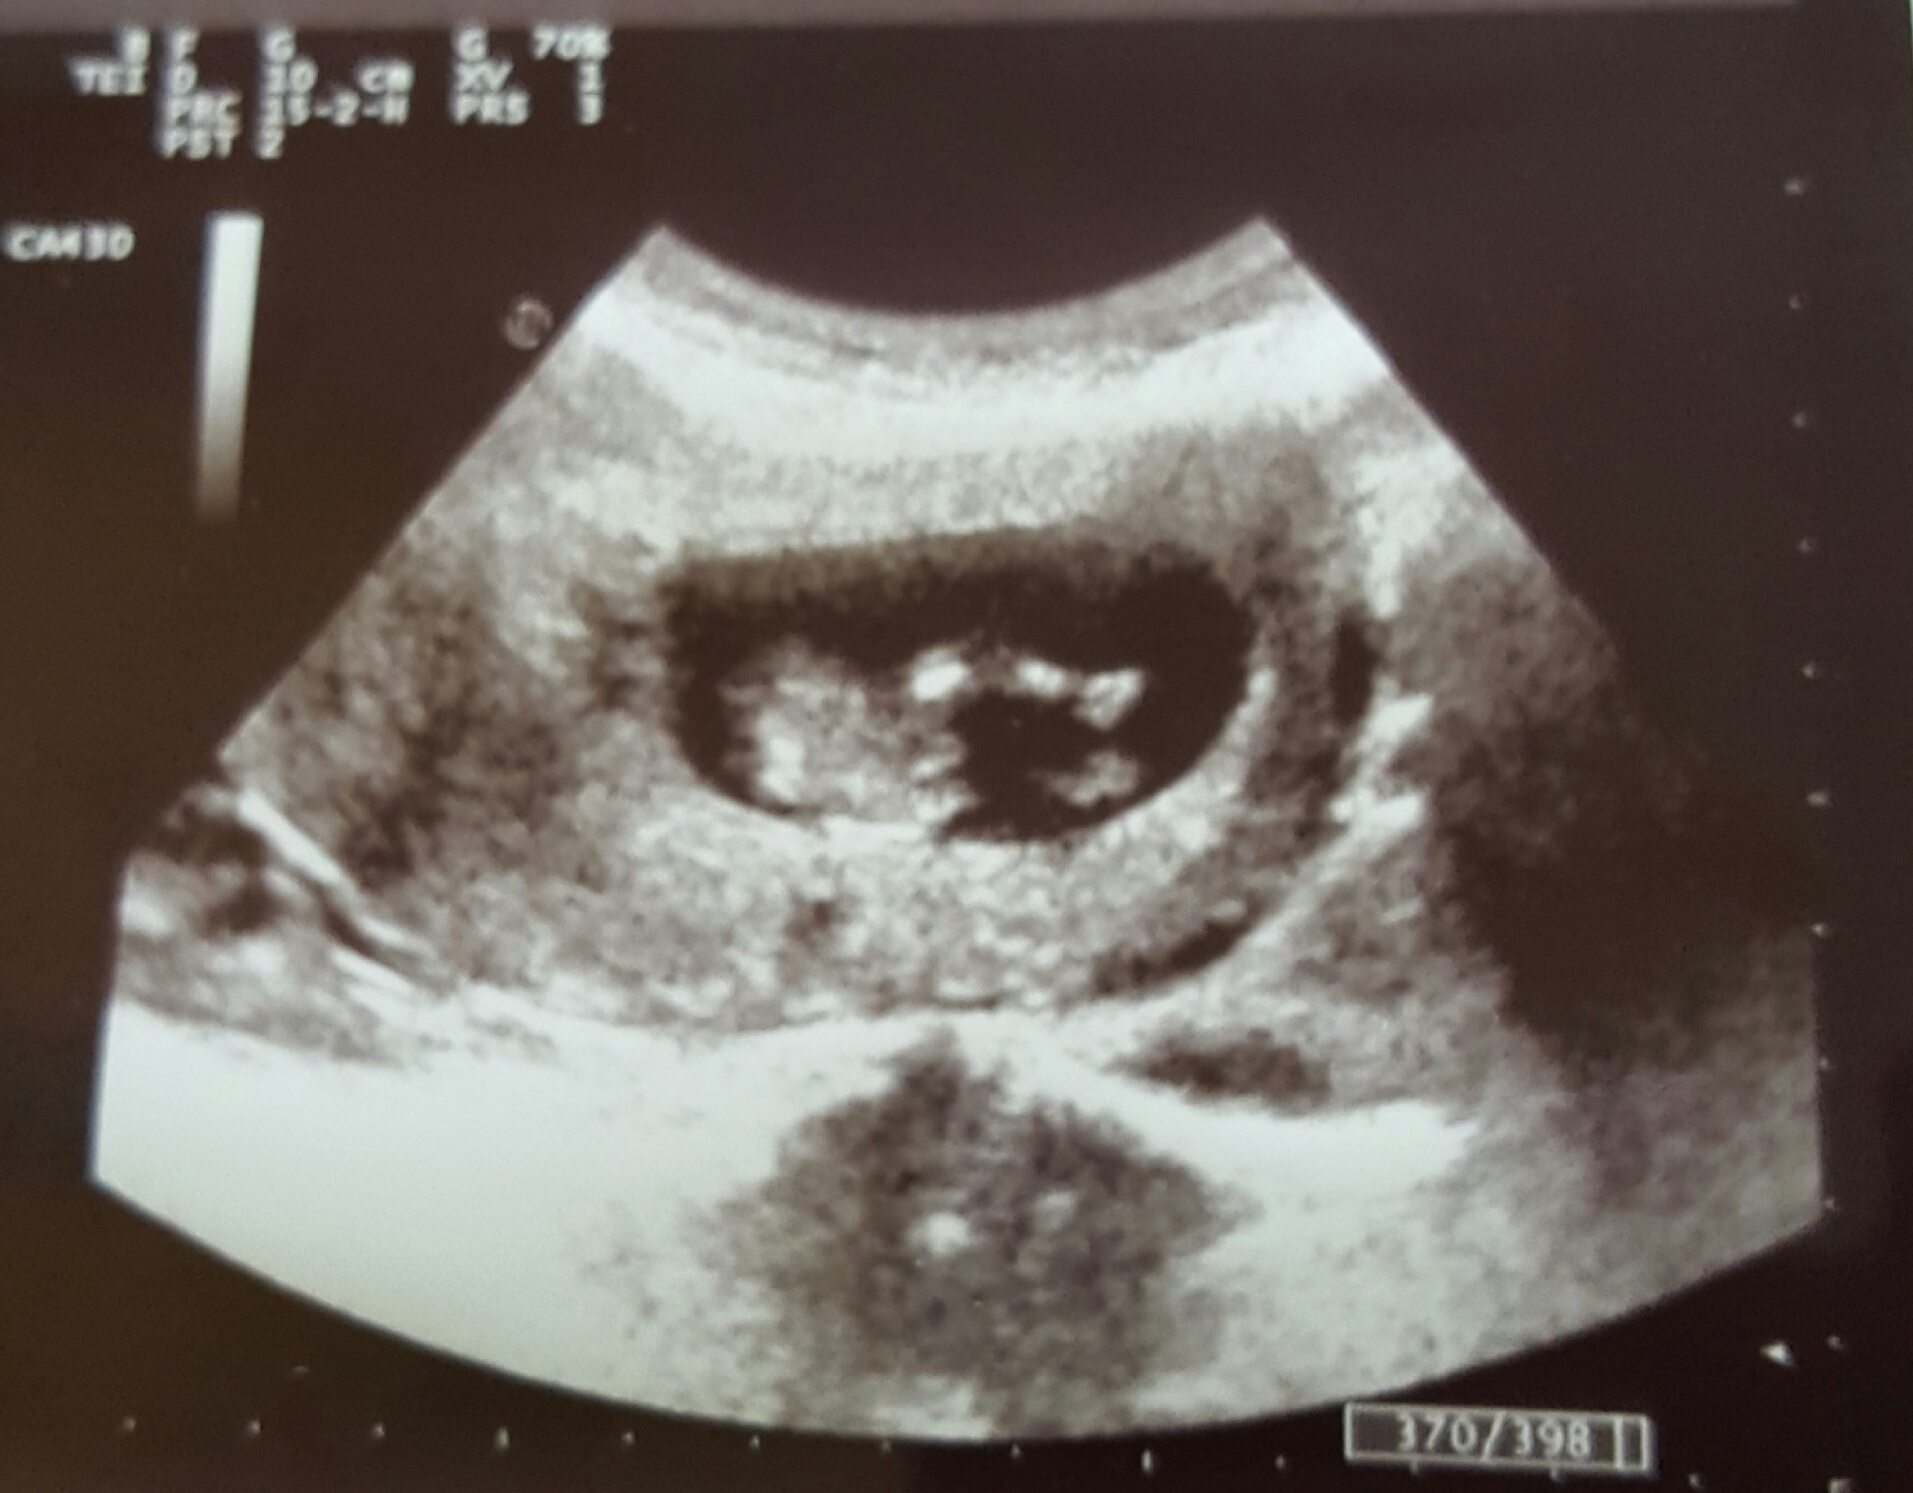

Anyway, I have a question about potty shots. I got this shot at 11 weeks 4 days but was measuring 12 weeks 4 days

..so I am not even sure what week it wud really be.

I most definitely see something like a penis there lol but the doctor was saying that at this stage it could just be the lower spine?

What do you guys think? And can anyone shed light on why potty shots aren't generally used at this stage, even if it seems so obvious that it's a boy?

Attachment 28544